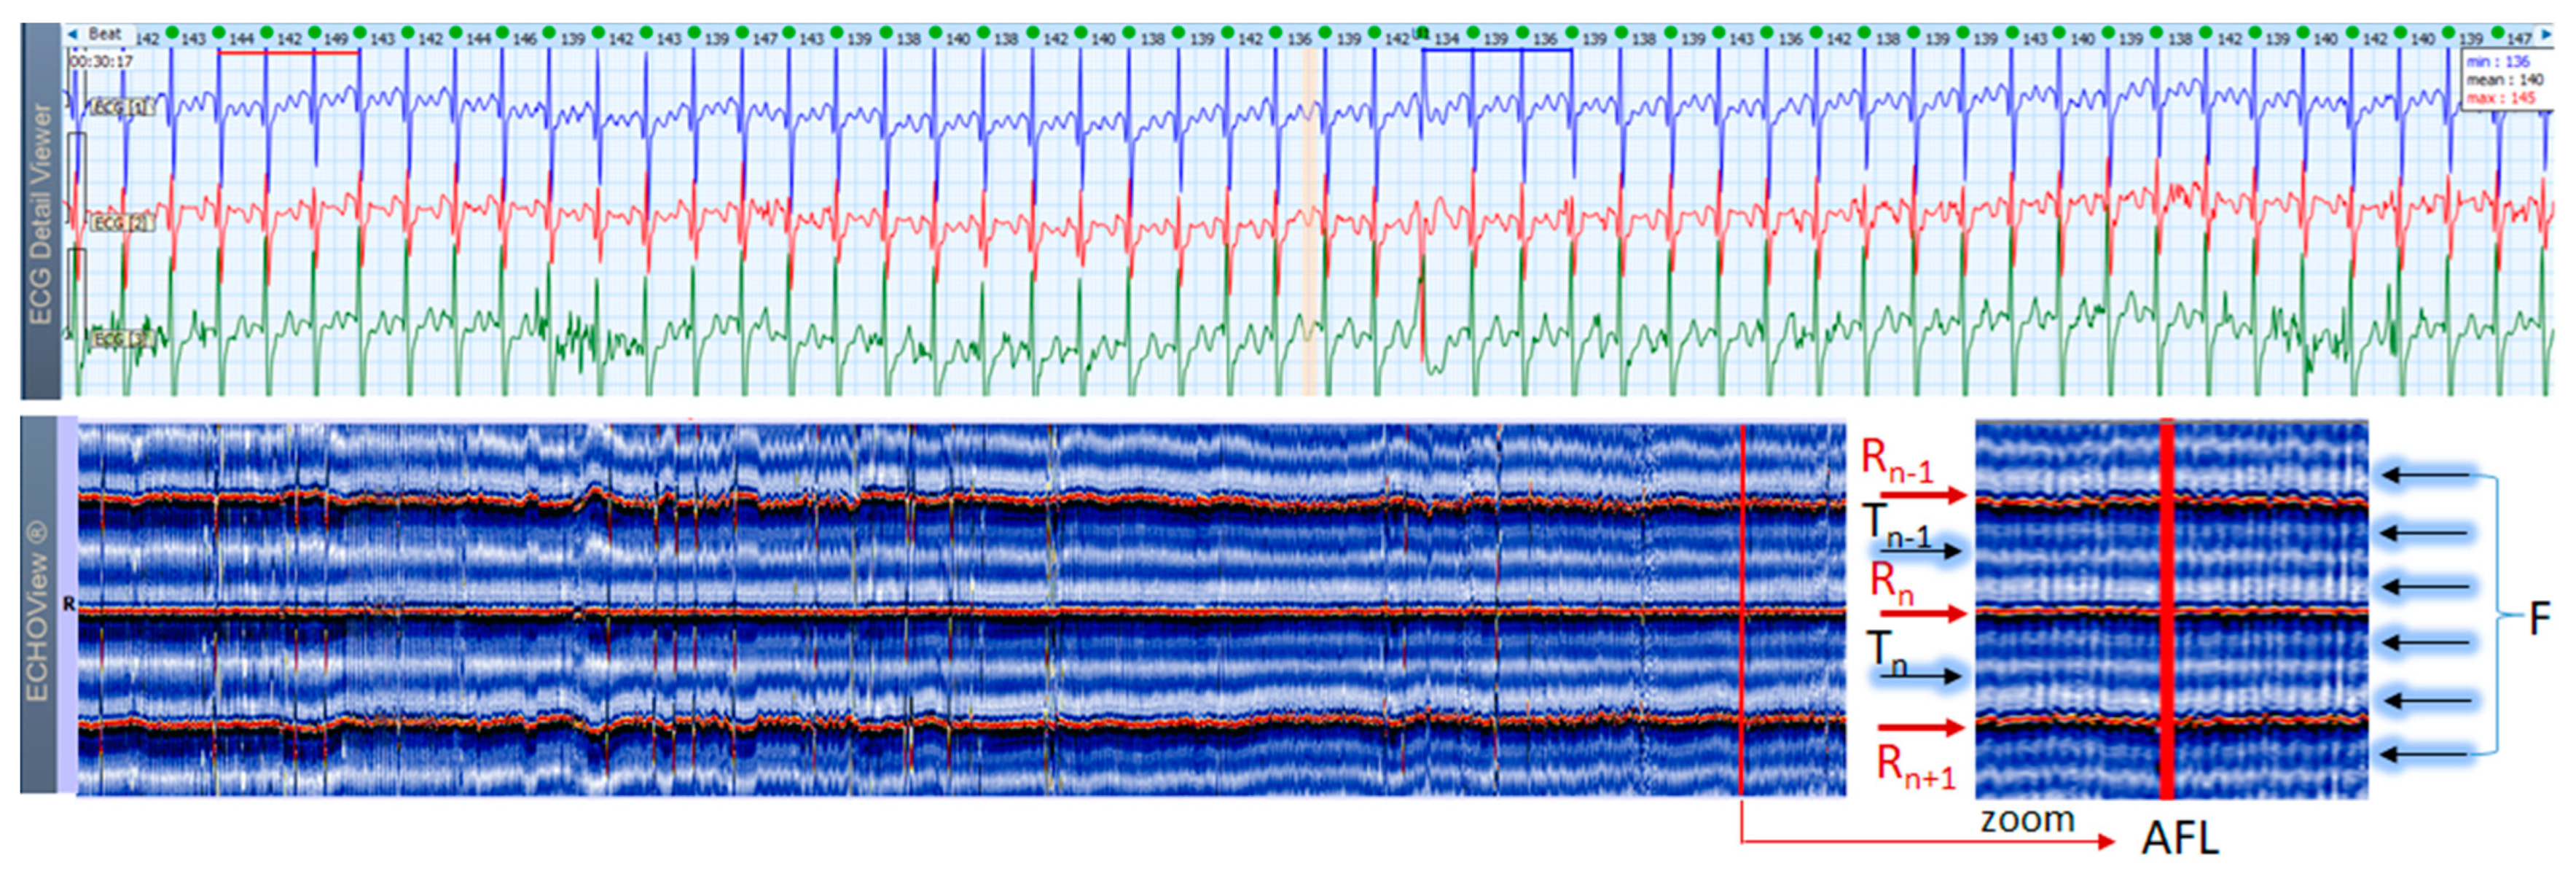

AF is the most common arrhythmia among humans (1 of 4 will have at least 1 episode of this arrhythmia in his/her life). This rhythm disorder and the less common AFL are usually not difficult to be recognized in standard 12-lead ECG strips if the ventricular rate is not too high and the fibrillation ‘f’ waves or flutter ‘F’ waves are visible in at least one lead. However, if HR is very high and irregularity of the rhythm, and fibrillations (in AF) or ‘saw-like’ fluctuations of the isoelectric line (in AFL) are not visible, it could be difficult to say what kind of arrhythmia the patient has. In addition, in many patients these arrhythmias are transitory and sought by Holter ECG/event recorders, which records frequently have a lot of artifacts due to physical activities and other factors. In such cases, ECHOView may help to recognize AF/AFL arrhythmias because they have a very characteristic pattern on the color map, as shown in Figure 13, Figure 14 and Figure 15. The notable behavior of AF is the absence of a P-wave band and scattered dots of R-wave peaks (Figure 13 and Figure 14), while AFL has presence of several F-wave bands and stable band of R-wave peaks (Figure 15). Beneficially, these ECHOView maps sufficiently differ from the patterns of other high-rate arrhythmia, such as SINT (Figure 6, Figure 7 and Figure 8), SVA (Figure 9) and PSVT (Figure 10, Figure 11 and Figure 12).

ECHOView interpretation turned out to be very important for some of our patients with episodes of supraventricular rhythm disorders such as SINT, SVT, AF and AFL. These arrhythmias are very common among the general population, affecting both younger and older people, with or without underlying cardiac injury [1,2,3,4,5,6,7]. A lot of non-cardiac conditions such as thyroid dysfunction, chronic lung diseases, electrolyte disturbances, infections (including COVID-19), etc. could also ‘unlock’ SVAs [1,2,8]. The diagnosis is based mostly on non-invasive ECG methods, mainly standard 12-lead ECG and 24–72 h Holter ECG monitoring [1,2,3,4,5,6,7,8,9,10]. Standard 12-lead ECG records are obtained in rest and their quality is usually much better than Holter ECG records, but conventional ECGs are not the ideal tool for diagnosing arrhythmias. They present time frames of about 10–20 s and many patients with SVAs could be missed because arrhythmias are often transitory [1,2,3,4,5,8]. For this reason, diagnosis is usually obtained by Holter ECG monitoring or event recorders [1,2,3]. However, most of these devices record less number of channels (1 to 3) in which P-waves of the normal sinus rhythm may not be demonstrated [1,2,3,4,5,6]. In addition, external factors such as movements, posture, skin contact of the electrodes, etc. may exert significant influence on the quality of the records and the morphology of ECG components, thus making the detection of P-waves even more difficult [1,8,17]. One of the most common ECG challenges is the differentiation of a high-rate sinus tachycardia from other SVTs (AVNRT, AVRT, focal AT) and sometimes from high-rate AF/AFL. Physical activities, emotions, panic attacks, pain/severe discomfort, febrility, etc. may cause expressed sinus tachycardia with complaints indistinguishable from a true tachyarrhythmia [3,5,9]. The ECG leads to shortening of the RR intervals, the impossibility of recognizing regularity/irregularity of the rhythm, and identifying/distinguishing the normal sinus P-wave from pathological P-waves of AT, F waves of AFL and f-waves of AF could make diagnosis uncertain, particularly if the patient has already had arrhythmias or risk factors for the development of them [5,7,9]. In this article we present several cases in which patient’s complaints and the Holter ECG records required differentiation between SINT, SVT and AF/AFL. In our cases, ECHOView facilitated the accurate diagnosis clearly disclosing the P-wave in SINT (Figure 6, Figure 7 and Figure 8) and the pathological atrial excitations in cases of true tachyarrhythmias SVT (Figure 10, Figure 11, Figure 12 and Figure 16), AF (Figure 13, Figure 14 and Figure 16) and AFL (Figure 15 and Figure 16) but also the contrastive ventricular pattern of NSVT. As the prognostic significance and therapeutic approach to arrhythmias can vary greatly [40], such as the need for oral anticoagulation in AF/AFL [1,2], the advanced perspective of ECHOView is an important tool to improve risk assessment and therapeutic decision-making.

4.3. ECHOView: Summary of the Principles of Imaging

The color-coded ECG amplitudes of sequential beats produce an intuitive trace of different intervals (PnRn, RnTn, Rn−1Rn, RnRn+1, etc.) in a visible image (width × height = 1740 beats × 1500 ms) within one ECHOView page. Without a specific measurement, this visual effect resembles the rendering of one-dimensional time trends of automatically measured ECG intervals. These trends show stable PnRn and RnTn intervals during the NSR part of the examples in Figure 4, Figure 5, Figure 6, Figure 7, Figure 8, Figure 9, Figure 10, Figure 11 and Figure 12. The trends are also informative for the RR-intervals (Rn−1Rn, RnRn+1) on a beat-by-beat basis that is helpful for identifying long-term HR changes in high-rate SINT (Figure 6, Figure 7 and Figure 8) and AFL (Figure 15), as well as rhythm, transitions NSR→ paroxysmal SVA (Figure 9), NSR→PSVT (Figure 10, Figure 11 and Figure 12), NSR→NSVT (Figure 10, Figure 11 and Figure 12), and AF→AFL→ST (Figure 16).